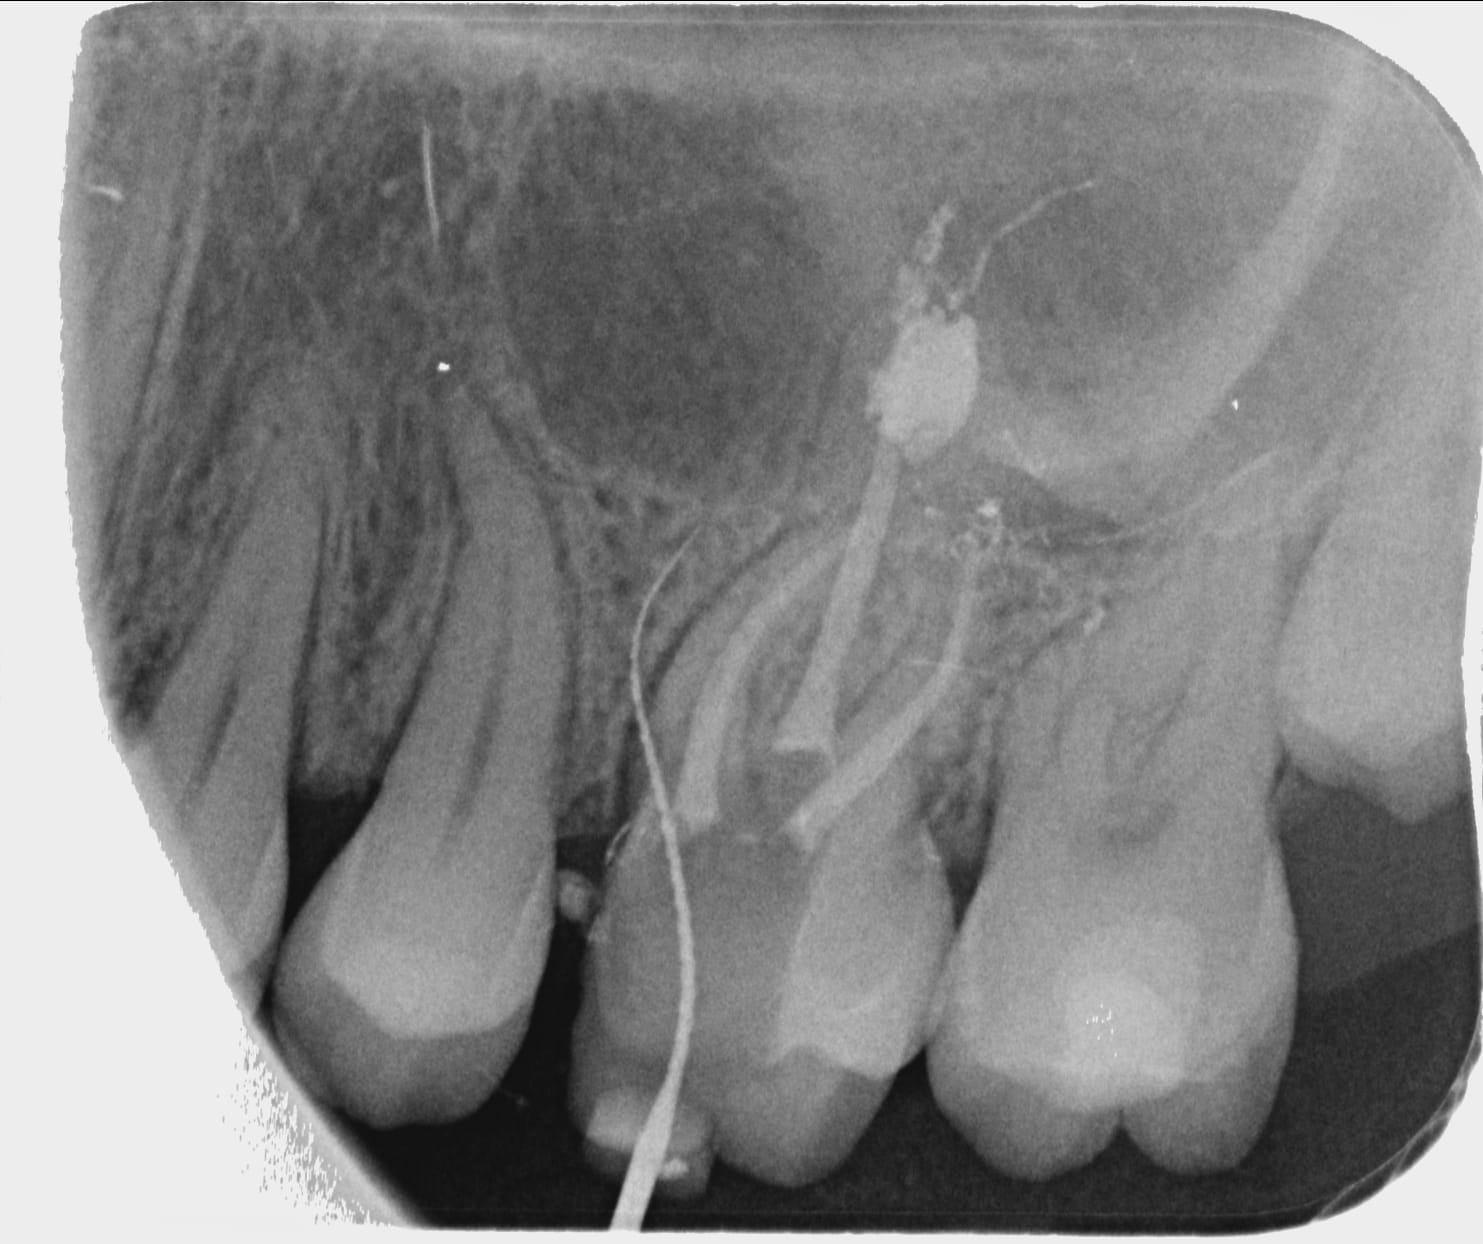

Patiente pas venue depuis trois ans qui revient suite douleur sur 26 prise par un confrere en urgence qui lui dit avoir devitalisé la dent et la patinete revient car toujours douleur et là catastrophe j'enleve le cavit et je comprends la cause des douleurs... mta ou avulsion?

Radio

Sur la radio, tu vois un colossal depassement de pâte en palatin, fais un CBCT et tu en sauras plus.

Mais pour moi, carie juxta-osseuse+depassement inoperable+douleurs= extraction...